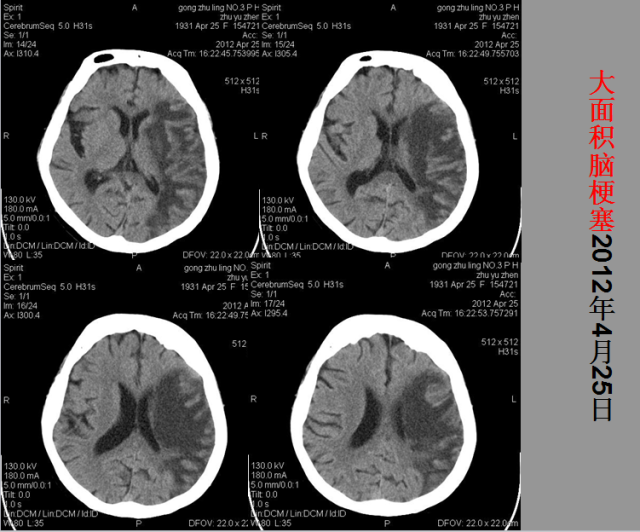

急性颅脑损伤篇

03